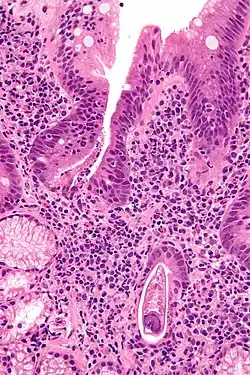

| Micrograph showing strongyloidiasis; a fragment of a worm is seen in the lower right hand corner. H&E stain. | |